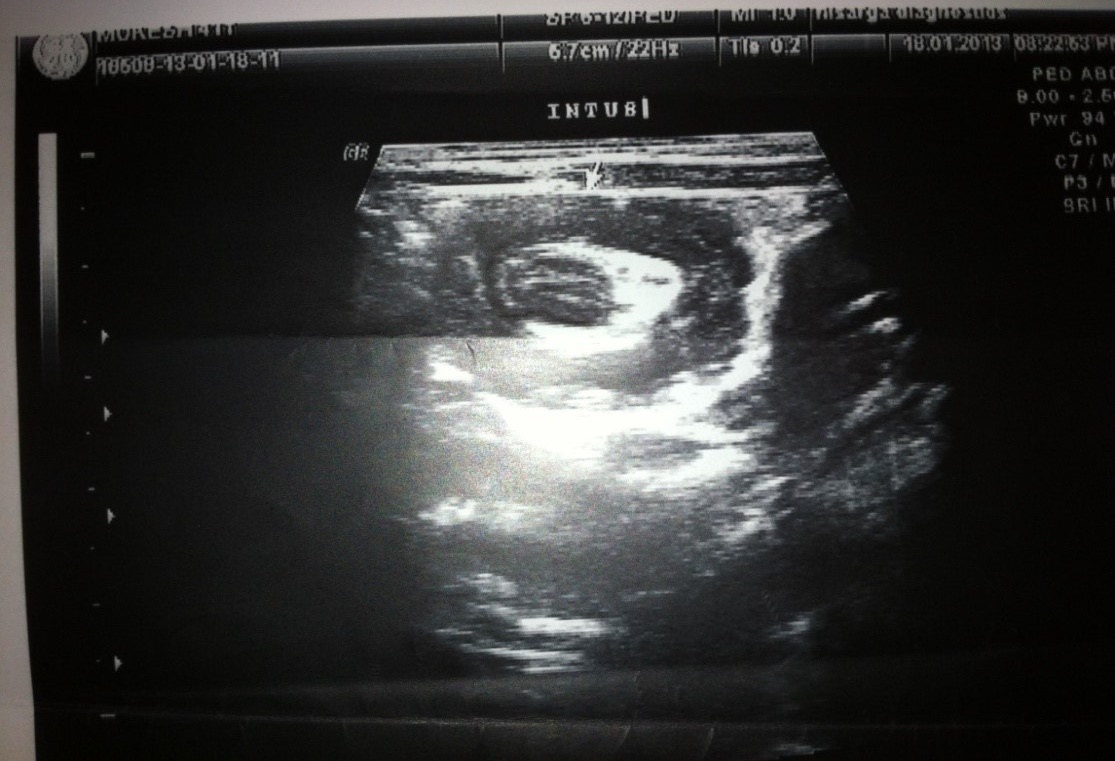

Ultrasonography:

• All patients underwent USG

• Doppler was used to determine bowel ischemia; guides reduction decisions

• Ultrasonography was diagnostic in 93% of our cases

USG |

Jejunoileal |

Ileocolic intussusception |

Abdominal ultrasound:

Replaced abdominal radiograph as primary screening modality

• Sensitivity 98 -100%; specificity 88 -100%

• Appearance: outer hypoechoic region surrounding an echogenic center or multiple concentric rings

• Use Doppler to determine bowel ischemia; guides reduction decisions

• Guide hydrostatic and pneumatic reduction